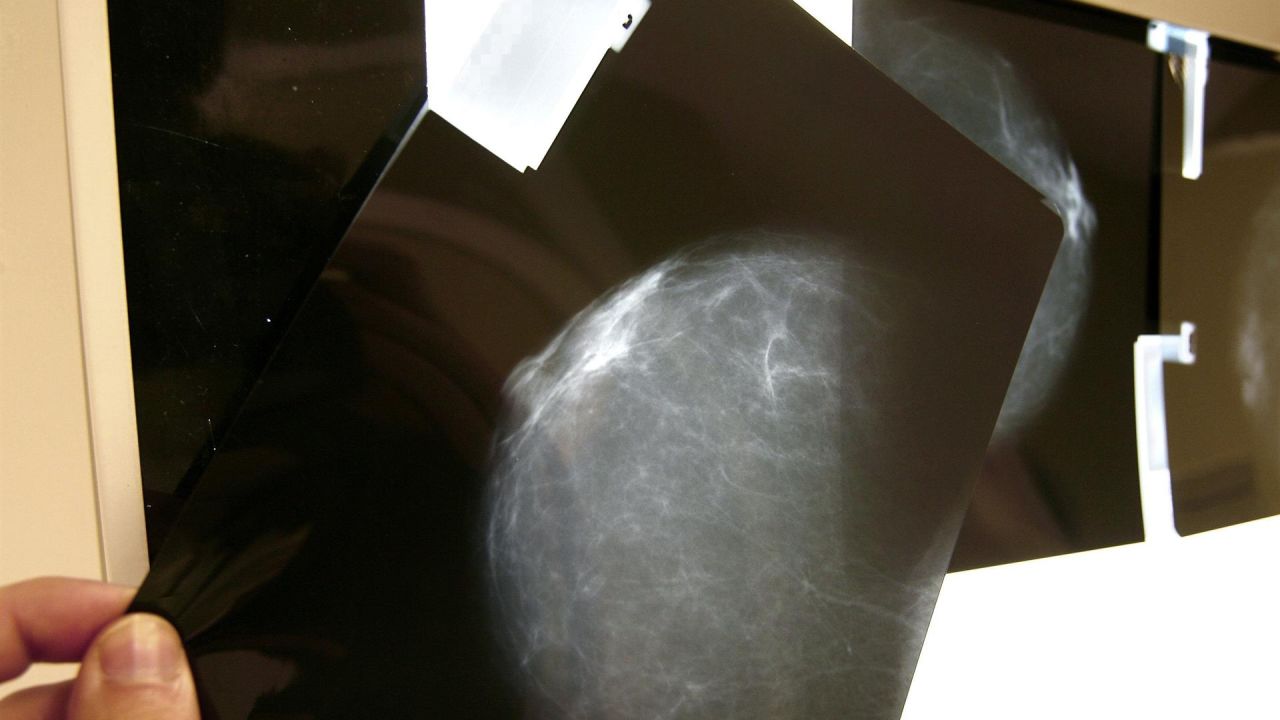

Un nuevo tratamiento contra el cáncer de mama permitirá evitar la quimioterapia

Un nuevo estudio internacional en el que participa España asegura que próximamente no se necesitará usar la quimioterapia como tratamiento en las mujeres con cáncer de mama.

La ciencia avanza a pasos agigantados y ahora es turno de mirar hacia adelante en tratamientos contra el cáncer. Hace unos días trascendía que Estados unidos había desarrollado un nuevo sistema para diagnosticar el cáncer de mama a 20 años vista. Y ahora España, en concreto el Instituto de Investigación Sanitaria Incliva del Hospital Clínico de València, ha querido formar parte del estudio internacional RxPONDER, que tiene una nueva misión: encontrar la manera de no usar la quimioterapia en pacientes con cáncer de mama.

La nueva fórmula propuesta, y ya probada con éxito en los primeros ensayos clínicos, es ofrecer un tratamiento hormonal en vez de quimioterapéutico asegurando un pronóstico igual de favorable y eficaz. Esto significa, que un importante porcentaje de pacientes con cáncer de mama podrían prescindir de los efectos adversos que tiene la quimioterapia.

Actualmente a las mujeres posmenopáusicas a las que se les diagnostica cáncer de mama HER2 negativo - que es el subtipo cáncer de mama más frecuente- y que con receptores hormonales positivos (RH+), se les suele tratar con quimioterapia y con hormonoterapia. Estos primeros ensayos han conseguido demostrar que este grupo de mujeres podrán beneficiarse de este tipo de tratamiento.

Cabe recordar que un alto porcentaje de las mujeres con cáncer de mama entran en el rango de mujeres posmenopáusicas. Los últimos informes de AECC- Asociación Española contra el Cáncer- afirman que en 2019 se diagnosticaron 33.307 nuevos casos y que el mayor número total de diagnósticos se encuentra en las mujeres de entre 45 y 65 años.

Más de 800 españolas participaron en los ensayos

El Grupo GEICAM de Investigación en el Cáncer de Mama ha contribuido al estudio con 792 mujeres afectadas por este cáncer de forma voluntaria, lo que supone casi el 20% del total de los participantes en el ensayo. Además, de los diferentes centros hospitalarios de la Comunidad Valenciana también participaron 66 mujeres.